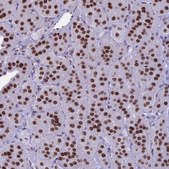

immunohistochemistry: 1:500-1:1000

The Human Protein Atlas project can be subdivided into three efforts: Human Tissue Atlas, Cancer Atlas, and Human Cell Atlas. The antibodies that have been generated in support of the Tissue and Cancer Atlas projects have been tested by immunohistochemistry against hundreds of normal and disease tissues and through the recent efforts of the Human Cell Atlas project, many have been characterized by immunofluorescence to map the human proteome not only at the tissue level but now at the subcellular level. These images and the collection of this vast data set can be viewed on the Human Protein Atlas (HPA) site by clicking on the Image Gallery link. We also provide Prestige Antibodies® protocols and other useful information.

- IHC tissue array of 44 normal human tissues and 20 of the most common cancer type tissues.